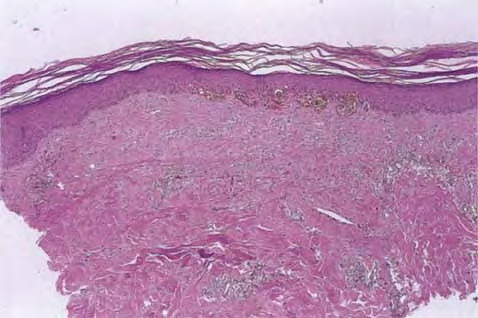

Recurrent nevus phenomenon = ظاهرةالوحمة الناكسة